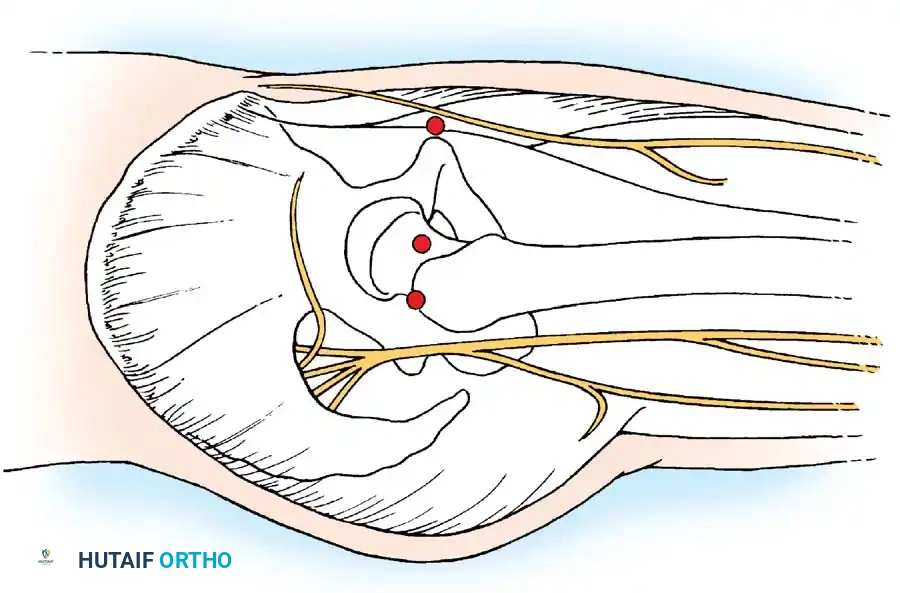

Arthroscopic Portal Anatomy and Safe Zones

1. The Anterolateral Portal (The Viewing Portal)

This is typically the first portal established, as it lies within the primary "safe zone."

- Location: Positioned just superior and anterior to the tip of the greater trochanter.

- Trajectory: An 18-gauge spinal needle is advanced toward the femoral head along a line 45 degrees medial and 45 degrees proximal.

- Anatomy Traversed: Penetrates the gluteus medius muscle.

- Structures at Risk: The superior gluteal nerve traverses approximately 4.4 cm cephalad to this portal. Staying close to the trochanteric tip ensures safety.

2. The Anterior Portal

Used primarily as a working portal for the anterior labrum and cam decompression.

- Location: Placed at the intersection of a vertical line drawn inferiorly from the anterior superior iliac spine (ASIS) and a transverse horizontal line drawn from the superior margin of the greater trochanter. Extended medially, this line sits just superior to the symphysis pubis.

- Anatomy Traversed: Penetrates the sartorius and rectus femoris muscles before entering the anterior capsule.

- Structures at Risk: The Lateral Femoral Cutaneous Nerve (LFCN) and the ascending branch of the lateral femoral circumflex artery.

Surgical Warning: To avoid transecting the LFCN, use a superficial skin incision only. Bluntly dissect and spread the subcutaneous tissues with a hemostat down to the capsule before passing the cannula. The blunt trocar will safely push the nerve aside.

3. The Posterolateral Portal

Used for viewing the posterior labrum and removing posterior loose bodies.

- Location: Just superior to the margin of the greater trochanter at its posterior border.

- Trajectory: Directed slightly cephalad and anteriorly, converging toward the anterolateral portal.

- Anatomy Traversed: Traverses the gluteus medius and minimus muscles.

- Structures at Risk: The sciatic nerve. It is imperative to have the hip in neutral rotation while establishing this portal to maximize the distance between the portal tract and the sciatic nerve.

- Accessory Portals: Three portals are typically required for complex arthroscopic labral repair: the anterolateral, the anterior, and a Distal Lateral Accessory (DLA) portal. The DLA portal provides the optimal trajectory for drilling suture anchors into the acetabular rim without penetrating the articular cartilage.